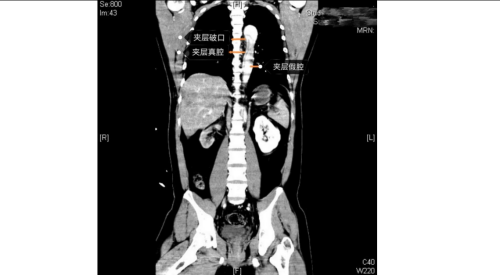

医院急诊科、麻醉手术科、外周血管介入科、急诊重症监护室等多学科团队火速响应。外周血管介入科主任、主任医师赵扬程及团队迅速评估患者病情并果断决定立即急诊手术。赵扬程指出,影像显示患者主动脉内膜严重撕裂,血流冲入血管壁形成巨大“假腔”。危急的是,夹层广泛累及腹腔主干血管,导致双下肢血管完全撕闭,下肢冰冷。此时主动脉壁薄如蝉翼,分秒间可致命破裂!同时,下肢及腹腔脏器严重缺血,如不迅速开通血管,将迅速引发肢体坏死、多器官衰竭。

手术室内,患者血压一度飙至惊人的320/150mmHg,循环濒临崩溃!麻醉团队全力稳定循环。在患者下肢几乎无法触摸到脉搏的极端条件下,外周血管介入科主任赵扬程及团队迎难而上,凭借精湛技术,精准置入支架,成功封堵主动脉内膜巨大破口,并精细重建了主动脉弓部受累的重要分支血管,恢复关键血流。这场持续近3小时的手术每一步都高风险且高度紧张,如同在死神面前进行“拆弹”。最终,这颗“血管炸弹”被成功拆除。